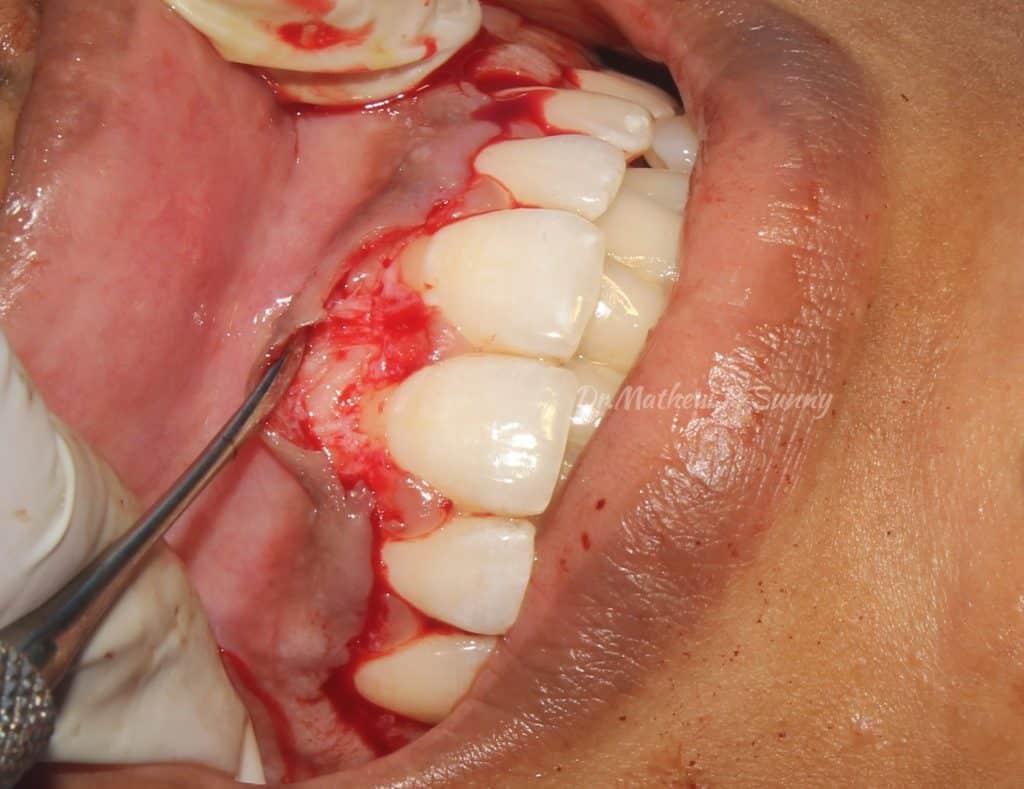

gingivectomy done initially to establish final gingival margin positions..

flap raised..